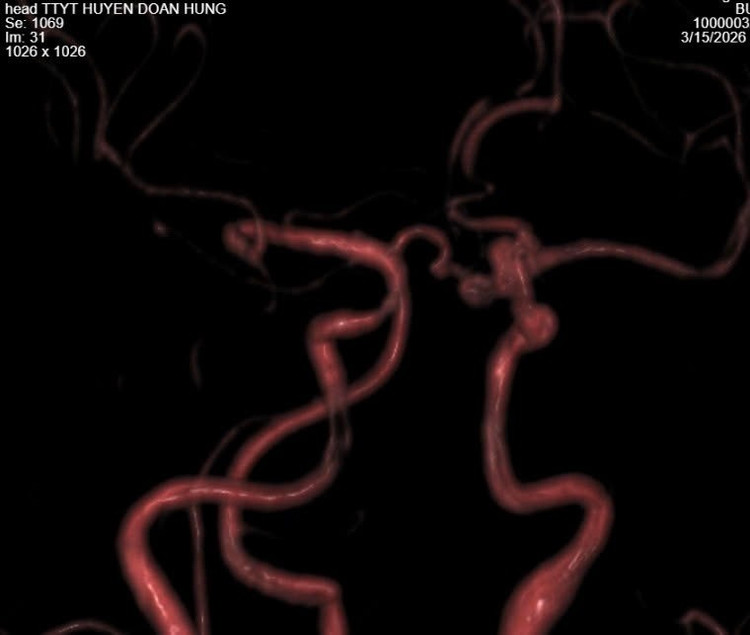

phinh-mach-nao-1.jpg

Mạch máu não bị phình - Ảnh BVCC